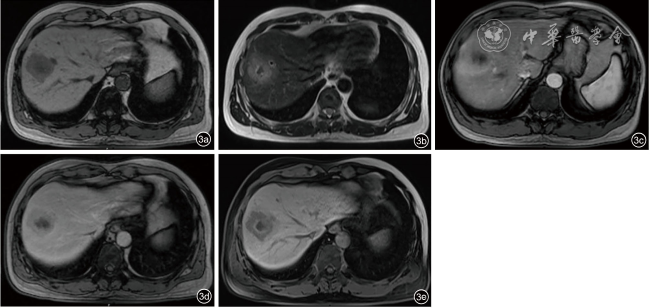

患者男性,42岁,右下腹酸胀疼痛3个月,无发热、寒战、周身黄染等其他症状,无肝炎病史。深圳市人民医院门诊CT检查发现肝右叶一类圆形低密度影,边界欠清楚,大小约4.5 cm×4.2 cm,增强扫描呈填充式强化,内壁欠光整,病灶内见小片状无增强区,动脉期病变周围见异常灌注(图1)。CT提示:肝右叶占位,考虑肝脓肿可能性大,肿瘤性病变待排查。实验室检查:直接胆红素浓度为8.5 μmol/L,总胆红素浓度为30.7 μmol/L,丙氨酸氨基转移酶40.1 U/L,碱性磷酸酶125 U/L,其余指标均在正常范围内。中性粒细胞比值、中性粒细胞绝对值在正常范围内,肿瘤标志物癌胚抗原、甲胎蛋白、糖类抗原199均阴性。入院行抗感染治疗1周后复查超声:肝右前、后叶交界处可见一大小约4.9 cm×4.6 cm实质性团块,形状欠规则,内部为不均质低回声,边界尚清楚,无声晕,彩色多普勒血流成像见团块周边较丰富血流信号,内部见少量血流信号。超声造影:经肘静脉团注造影剂2.4 ml,14 s肿块周边实质呈快速不均匀增强;24 s达峰值,中央可见无增强区,范围2.6 cm×1.5 cm;于门脉期早于周边实质开始消退,延迟期进一步消退(图2);结合超声造影提示:考虑肝细胞癌可能,肝脓肿待排查。进一步行磁共振造影检查:肝右叶见大小4.9 cm×3.5 cm类圆形长T1稍长T2信号影,弥散明显受限,中央见小片状长T1短T2区域,中央区域弥散未见受限,增强扫描病灶各期呈环形强化,中央未见明显强化,肝胆期未见明显造影剂摄取(图3),诊断:考虑肝脓肿,纤维板层样肝癌待排查。此后1周内多次复查腹部超声,均提示肝占位病变无明显变化,临床排除肝脓肿可能,考虑肝细胞癌可能性大。遂行机器人辅助腔镜下肝S8段切除术。常规病理:肿瘤大小4.0 cm×4.0 cm×3.5 cm,与周围肝组织界限尚清楚,在大量淋巴细胞、浆细胞、组织细胞及多核巨细胞的背景下,见梭形滤泡树突样或纤维母细胞样细胞呈条束状分布,核空泡状、核仁明显,可见多灶性坏死;免疫组织化学检测结果显示肿瘤细胞CD21(+)、CD23(+)、CD35(+)、SSTR2(+)、SMA(-)、CD3(-)、CD20(-)、CD138(浆细胞+)、Ki-67(20%+)、IgG4/IgG(<40%);原位杂交结果:EB病毒(Epstein-Barr virus,EBV)壳抗原IgA抗体阳性[EBV脱核RNA(Epstein-Barr virus enucleated RNA,EBER)+]。最终病理诊断为EBV阳性炎性滤泡树突细胞肉瘤(EBV+ inflammatory follicular dentritic cell sarcoma,EBV+IFDCS)。术后未进行放化疗,随访16个月未见肿瘤复发及转移。

图3 肝病灶磁共振成像。图a:T1加权成像呈不均匀低信号;图b:T2加权成像呈不均匀高信号;图c为动脉期,图d为门脉期,图e为肝胆期。图c~e:增强扫描病灶各期呈环形强化,中央未见明显强化,肝胆期未见明显造影剂摄取

结合文献9,10,11复习,EBV+IFDCS影像学表现为单发肿块,较大肿块多合并坏死、囊性变,偶见钙化,彩色多普勒超声可显示肿块周边较丰富的血流信号,内部血流信号稀少,无癌栓及血栓表现。CT增强扫描多表现为动脉期不均匀增强、填充式强化,部分病例表现为周边环形强化,门脉期、延迟期消退不明显或轻度消退,中部可见无强化的坏死区。磁共振检查T1加权成像表现为均匀、不均匀低信号,T2加权成像表现为均匀、不均匀高信号,可见环状低信号包膜,增强扫描动脉期边缘结节状强化,门脉期及延迟期稍向中央填充,延迟期强化稍减退。陈阳阳等12认为磁共振更有优势和价值,肿瘤实性成分弥散加权成像均呈高信号,表观扩散系数序列成像呈低信号,与相应脾一致,这一特征有助于诊断和鉴别诊断。谢品楠等13回顾分析了12例脾EBV+IFDCS患者的CT增强特征:表现为不均匀强化,门脉期持续强化,延迟期缓慢消退。这说明EBV+IFDCS的影像学表现存在多样性,容易误诊。本例患者CT、磁共振均提示肝脓肿可能,而超声造影显示肿块在动脉早期增强,在门脉期、延迟期可见轻度消退,呈快进快退特征,符合肝恶性肿瘤超声造影增强表现。临床在抗感染治疗无效后最终接受超声诊断,选择手术处理。既往病例未见超声造影特征报道,超声造影对肝EBV+IFDCS的诊断价值有待进一步研究。